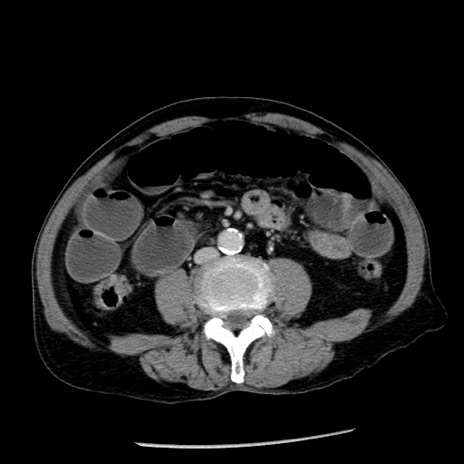

症例26(横断像)

【症例】80歳代男性

【主訴】嘔吐

【現病歴】昨晩2回嘔吐あり、今朝になっても嘔吐あり。来院。

【既往歴】胃潰瘍

【身体所見】意識清明、BT 37.6℃、BP 166/95mmHg、HR 100bpm、SpO2 97%、腹部:平坦・軟、腸蠕動音聴取良好、圧痛なし。

【データ】WBC 21900、CRP 1.46